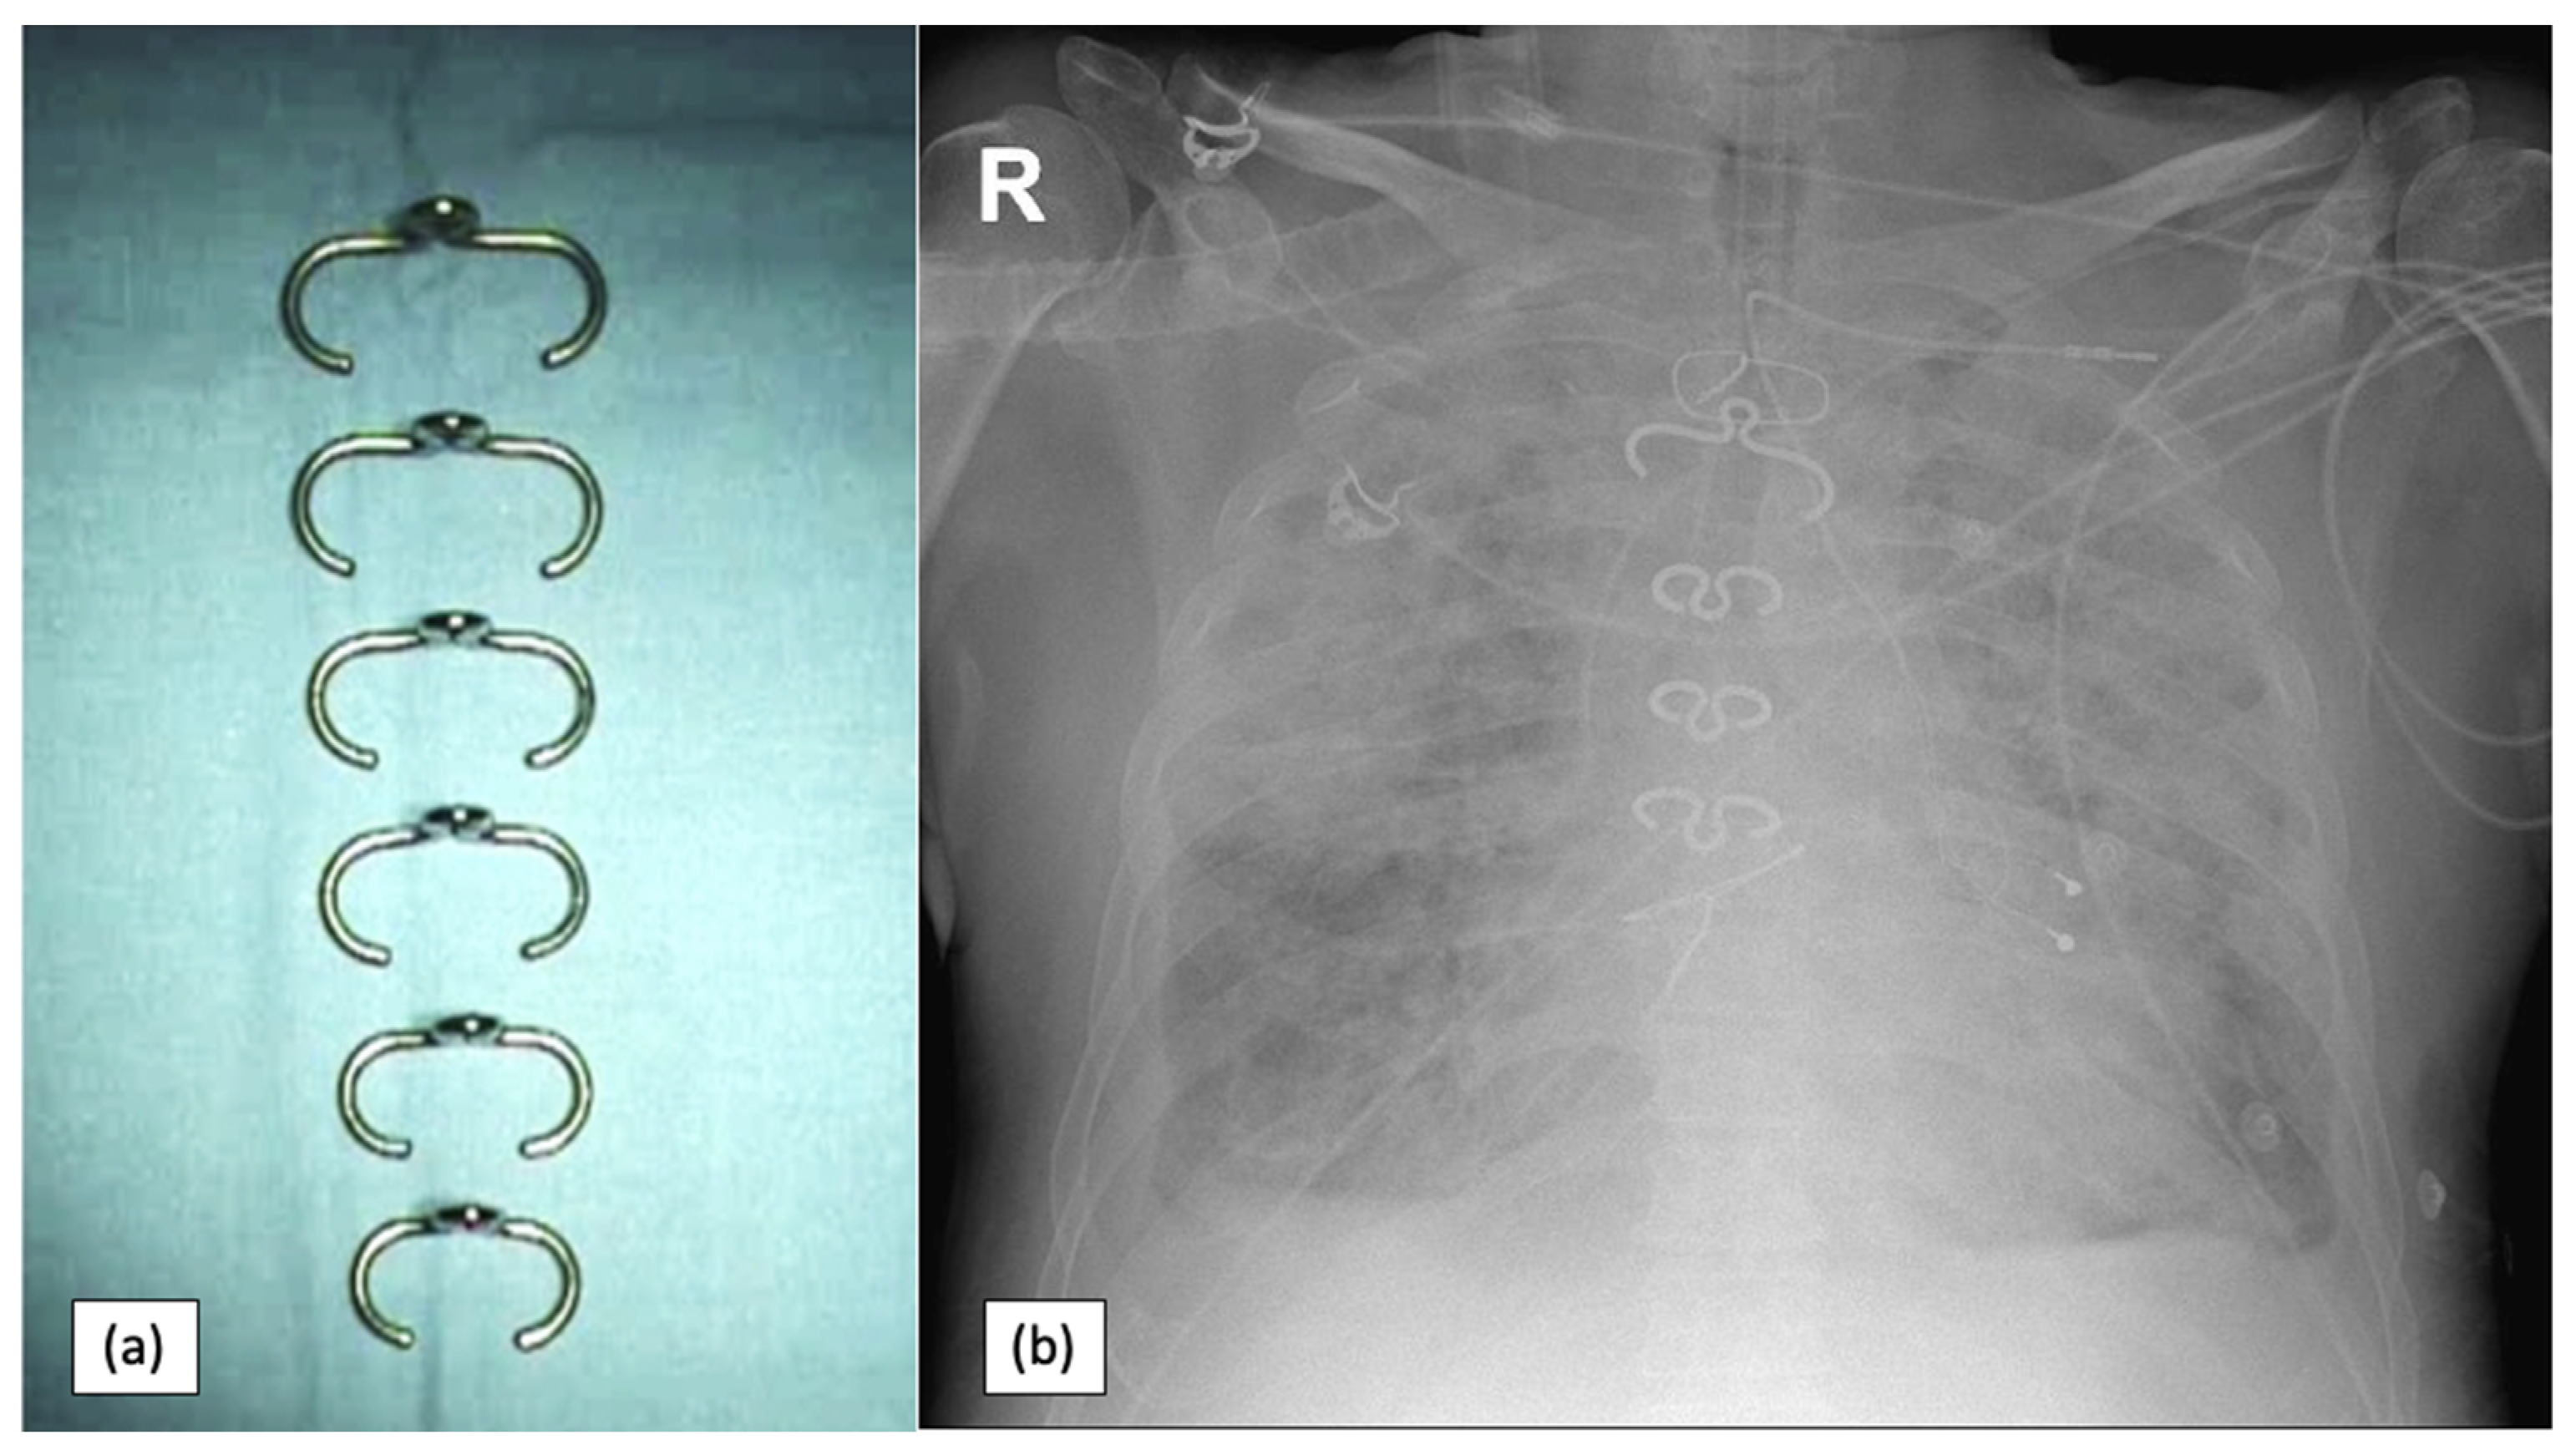

- Jolly, S.; Flom, B.; Dyke, C. Cabled Butterfly Closure: A Novel Technique for Sternal Closure. Ann. Thorac. Surg. 2012, 94, 1359–1361. [Google Scholar] [CrossRef] [PubMed]

- Antonič, M.; Petrovič, R.; Miksić, N.G. Thermoactive Nitinol Clips as Primary and Secondary Sternal Closure after Cardiac Surgery—First Experience in Slovenia. Acta Clin. Croat. 2021, 60, 435–440. [Google Scholar] [CrossRef] [PubMed]

- Stelly, M.M.; Rodning, C.B.; Stelly, T.C. Reduction in deep sternal wound infection with use of a peristernal cable-tie closure system: A retrospective case series. J. Cardiothorac. Surg. 2015, 10, 166. [Google Scholar] [CrossRef] [PubMed][Green Version]